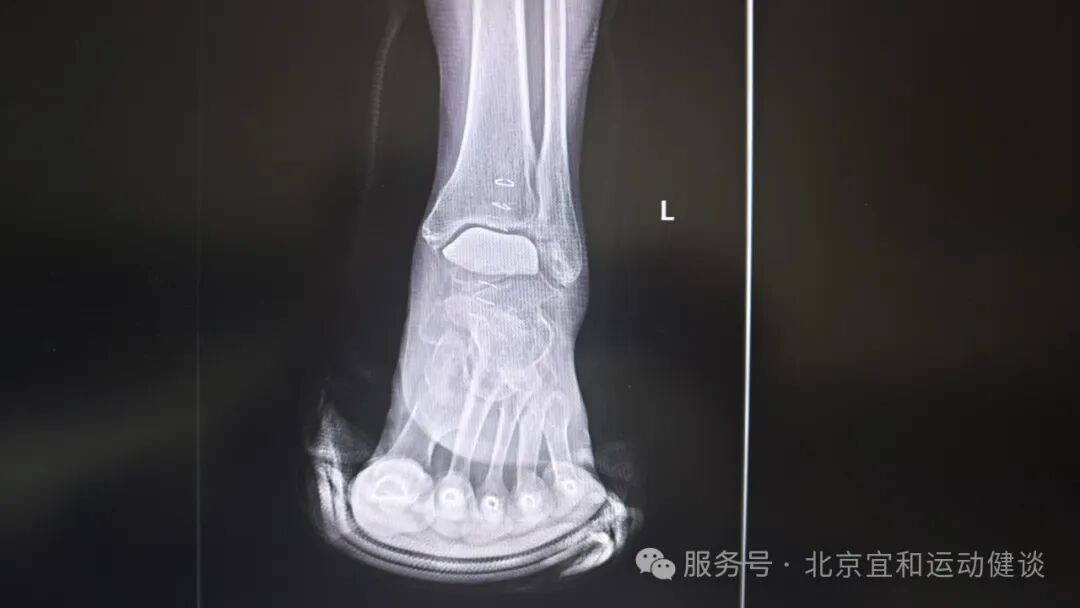

患者术后4周复查影像学资料